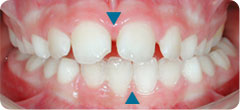

Case: The lower midline is deviated to left because of mandibular shift (see the blue triangles). Lower jaw is forced to grow asymmetrically, to the left.

Before